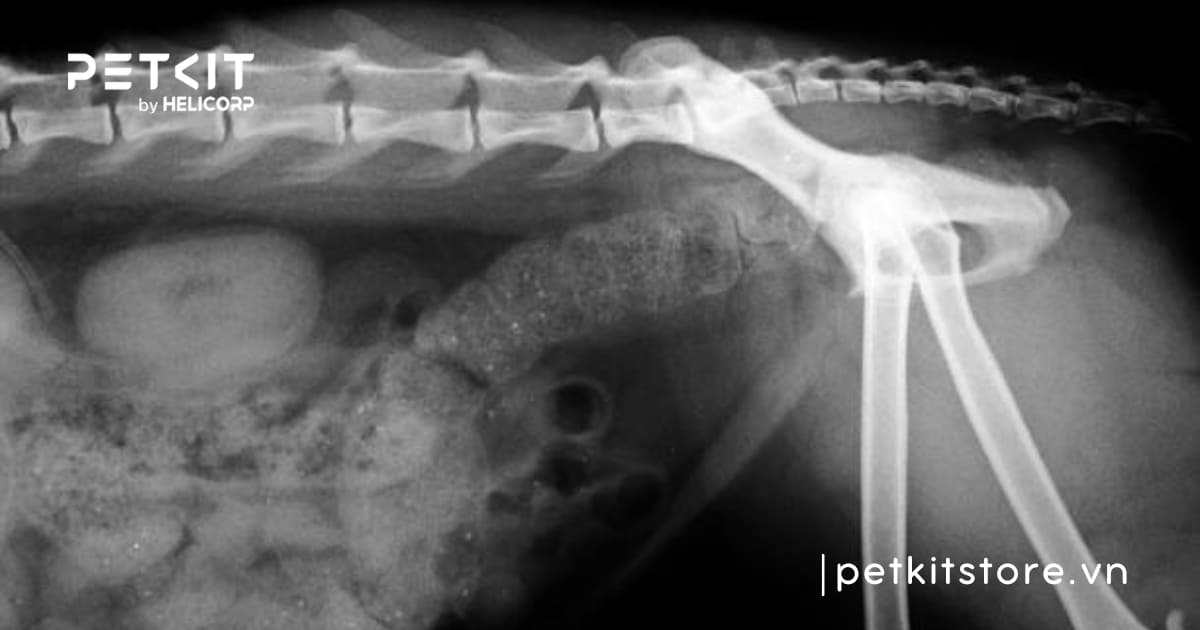

1.3 Bụng cứng hoặc sưng to

Một trong những dấu hiệu mèo bị táo bón là bụng bé bị căng to và cứng. Tình trạng này do ruột mèo không thể đào thải phân một cách tự nhiên, phân sẽ tích tụ lại và khiến bụng mèo bị sưng lên. Nếu để lâu ngày, phân sẽ tích tụ nhiều gây đầy bụng và không thoải mái, dẫn đến việc mèo mất cảm giác thèm ăn hoặc chỉ ăn rất ít. Điều này có thể ảnh hưởng trực tiếp đến sức khỏe tổng thể của “boss”.

Tích tụ chất thải lâu ngày khiến bụng mèo sưng to và cứng